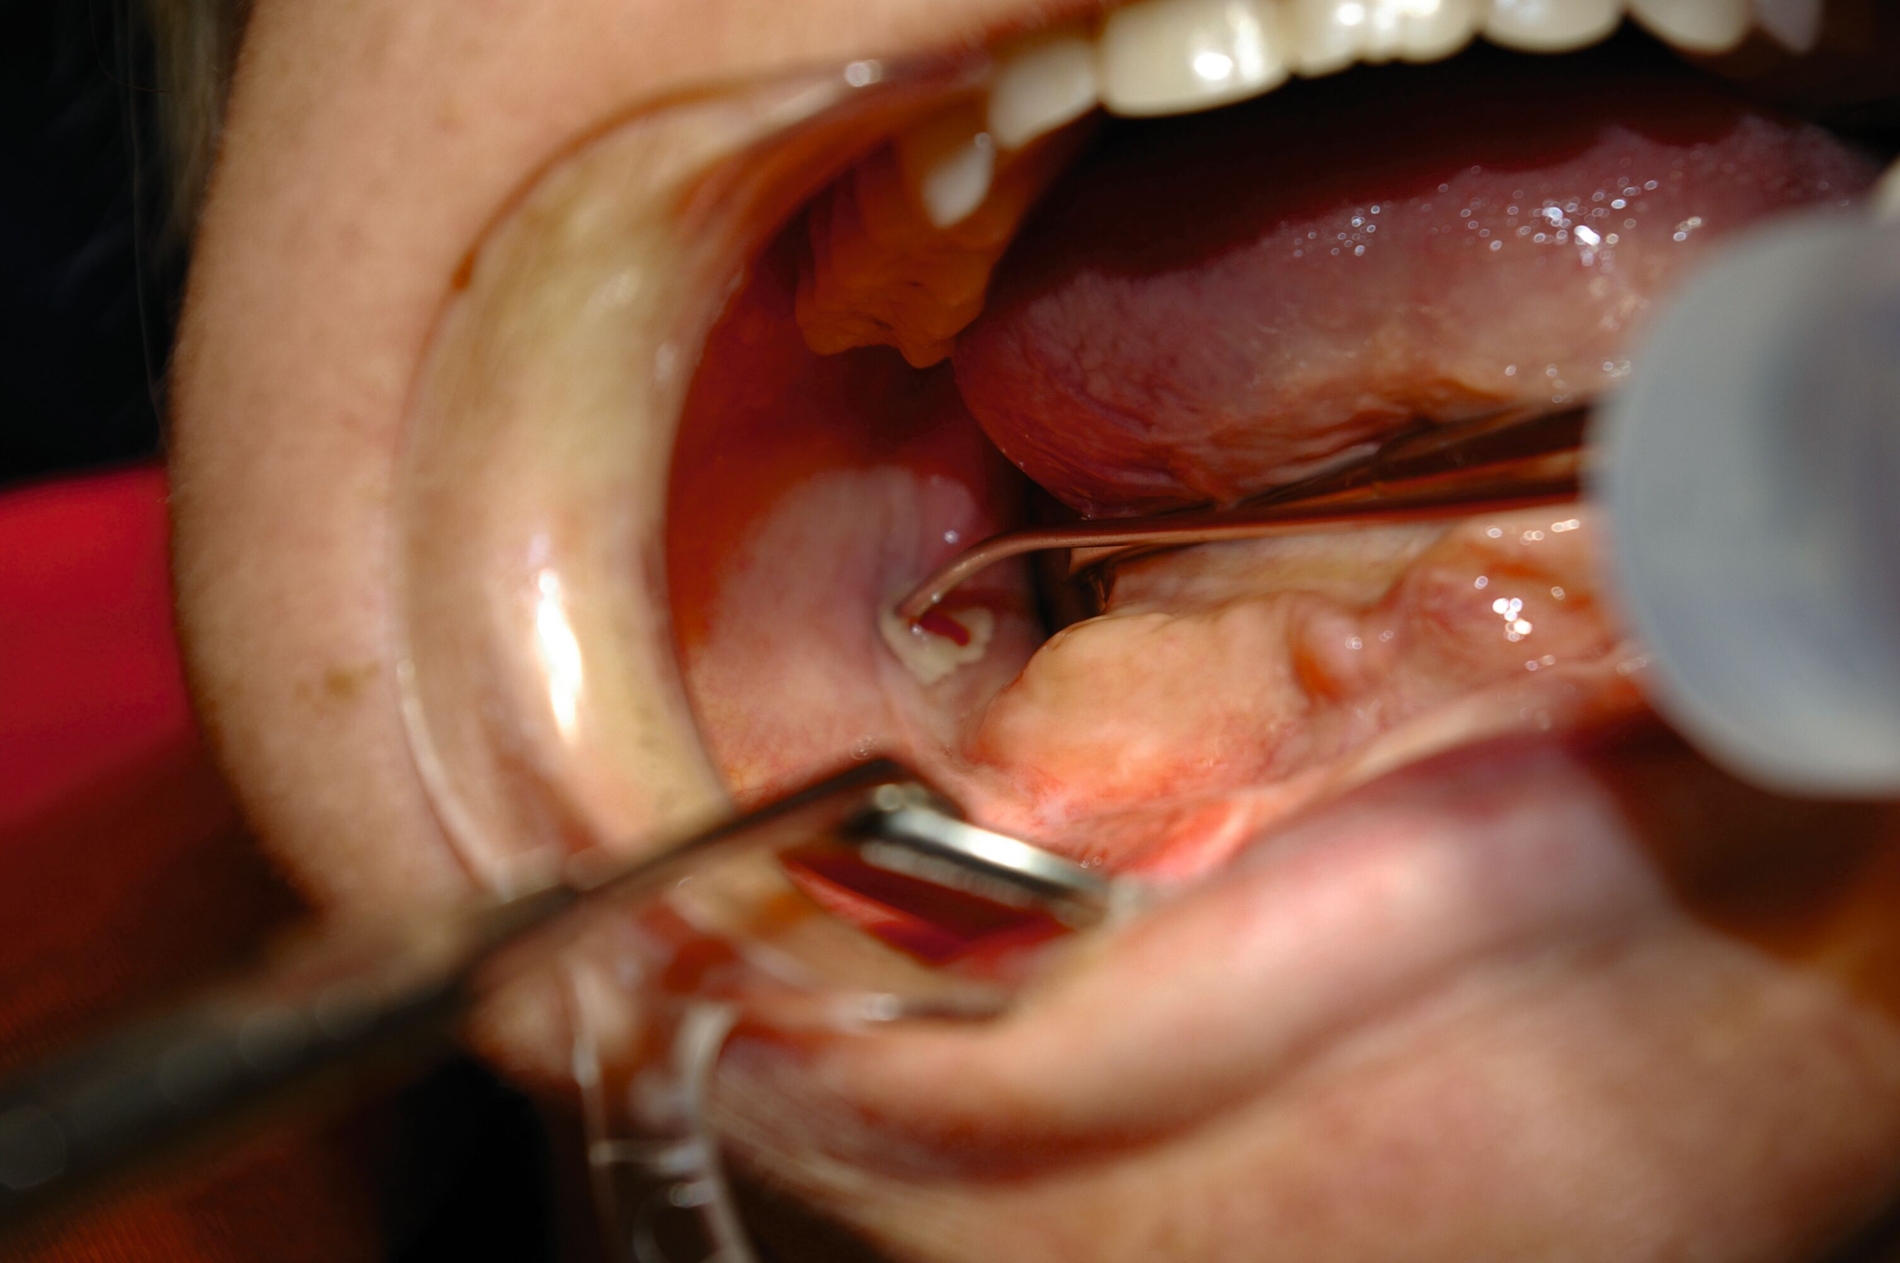

In der klinischen Untersuchung imponiert extraoral rechtsseitig ein muskulärer Tonusverlust mit Bell‘schem Phänomen sowie intraoral ein hochstehender Mundboden der Gl. sublingualis hinter einem palpatorisch breit wirkenden anterioren Alveolarfortsatz. Im rechten Kieferwinkel findet sich lingual eine suppurierende Fistel (Abbildung 3).

Nach Lokalbehandlung der akuten Entzündung erfolgt in nasaler Intubationsnarkose (ambulantes MedizinZentrum Lichtenberg, Sana-Klinikum Berlin) die Entfernung des kariösen retinierten Zahns mit Ausräumung der Entzündung. Der blande, hochretinierte Distomolar wird ebenso wie die Zähne der Gegenseite belassen, die Resektionshöhle im rechten Kieferwinkel mit Beckenkammspongiosa verfüllt.